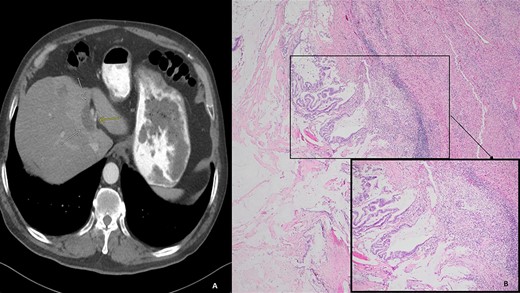

We present a case of a 74-year-old male who presented in 2018 with abdominal pain and underwent a series of cross-sectional imaging (CT-scan) which revealed an obstructed left bile duct and an associated mass. Follow-up esophagogastroduodenoscopy (EGD) and endoscopic ultrasound (EUS) confirmed the presence of a mass at the confluence of the bile ducts with possible liver invasion (Fig. 1A). A needle aspiration done was suspicious for carcinoma. Patient underwent diagnostic laparoscopy which revealed no evidence of metastatic disease, therefore, an extended left hepatectomy with a roux-en-y hepaticojejunostomy was performed. On pathological evaluation of the specimen, invasive mucinous adenocarcinoma with an intraductal papillary mucinous component, in a background of high-grade dysplasia was found involving the left hepatic lobe (Segment 4b) and left hepatic duct (Fig. 1B). Surgical margins were negative for carcinoma. No lymphovascular, perineural or lymph node involvement was seen. The tumor was classified as pT1a, pNx R0 according to the American Joint Committee of Cancer (AJCC) 8th edition.

(A) Computed tomography (axial): ovoid low-density mass contiguous with dilated left hepatic bile duct. (B) Histology: invasive mucinous adenocarcinoma with an intraductal papillary mucinous component, in a background of high-grade dysplasia was identified involving the left hepatic lobe (segment 4b) and left hepatic duct.